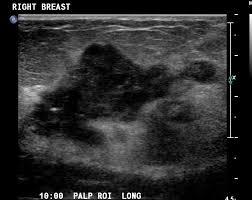

Ultrasound imaging allows better evaluation of the status of the axillary lymph nodes in patients with ibc, an important step in determining extent of disease prior to initiation of chemotherapy. However, a dark spot on your ultrasound doesn't mean that you. It is the most common cause of cancer death in women. in 2005 alone, 519 000 deaths were recorded due to breast cancer. this means that one in every 100 deaths worldwide and almost one in every 15 cancer deaths were due to breast cancer. On ultrasound, a breast cancer tumor is often seen as hypoechoic, has irregular borders, and may appear spiculated. In the table the differences in ultrasound appearances are listed.

Molecular Markers Pathology And Ultrasound Features Of Invasive Breast Cancer Clinical Imaging from els-jbs-prod-cdn.jbs.elsevierhealth.com Sometimes breast cancer can look like a fibroadenoma and fibroadenomas can look like a cancer on ultrasound. What does the doctor look for on a mammogram? cancer.org. You can get dressed straight after the ultrasound. On ultrasound, a breast cancer tumor is often seen as hypoechoic, has irregular borders, and may appear spiculated. When is breast ultrasound used? Benign and malignant characteristics of breast lesions at ultrasound allow the classification as either malignant, intermediate or benign based on work published by stavros et al. Ultrasound characterization of breast masses. indian journal of radiology and imaging. However, a dark spot on your ultrasound doesn't mean that you.

Cysts, tumors, and growths will appear as dark areas on the scan. Breast ultrasound uses sound waves to make a computer picture of the inside of the breast. What does a solid mass look like in an ultrasound breast image? Ultrasound of triple negative breast cancer. This is a network of thin tubes (vessels) and nodes that carry a clear fluid called lymph around the body. A breast ultrasound is most often done to find out if a problem found by a mammogram or physical exam of the breast may be a cyst filled with fluid or a solid tumor. Solid lesions can be a little brighter or darker than the surrounding tissue, and the way to evaluate these on ultrasound is to look closely at the margins or the outer edges of the nodule. In the table the differences in ultrasound appearances are listed. Ibc is a rapidly progressive, aggressive form of breast cancer associated with a low overall survival rate. On the flip side, there are benign (not cancerous) breast changes which can mimic breast cancer as well. What does breast cancer look like on a mammogram? American cancer society, 9 oct 2017. Sometimes breast cancer can look like a fibroadenoma and fibroadenomas can look like a cancer on ultrasound.

Any area that does not look like normal tissue is a possible cause for concern. Below are images of dcis on breast ultrasound. Ultrasound is not used on its own as a screening test for breast cancer. Ultrasound (us) shows an irregular, hypoechoic (dark gray) spiculated mass (arrow), highly suspicious for cancer. This is because it may miss some early signs of cancer.